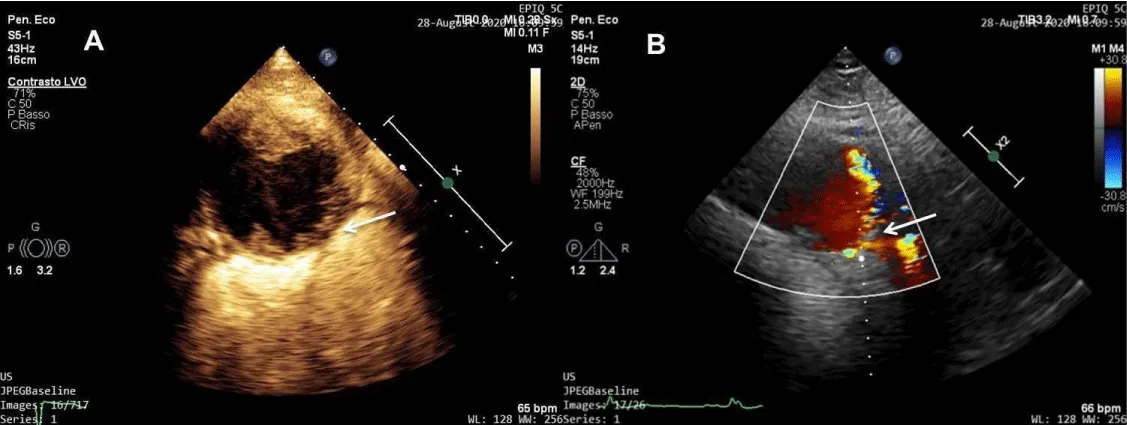

We performed echocardiography that showed normal size and function of the left ventricle and confirmed the presence of a giant round cystic-appearance lesion at the level of the right atrioventricular groove with mild compressive effect on the right chambers. The lesion was characterized by the presence of an anechoic space with an internal echogenic swirling flow pattern (Figure 2). The color Doppler mode showed a faint signal, without clear evidence of flow origin and it was not possible to sample any conclusive PW-Doppler signal.

Figure 2: 2D echocardiography (4 chamber view) shows the presence of a giant round cystic-appearance lesion characterized by the presence of an anechoic space with an internal echogenic swirling flow pattern.

To better characterize the lesion, we decided to use an echocardiographic contrast agent (SonoVue®), which showed a clear pattern of blood flow inside the mass with a probable origin at a very limited region (Figure 3a,3b, Video 1). At that level, it was also possible to sample an ECG-synchronized system-diastolic pulse-wave (PW)-Doppler pattern (with peak velocity 125 cm/s), typical for a coronary artery flow.

Figure 3: (a) Contrast echocardiography shows a clear pattern of blood flow inside the mass with a probable origin at a very limited region (white arrow). (b) Color Doppler signal shows the flow origin (white arrow).